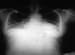

Hypertension is the most common primary diagnosis in the United States. [3] It affects approximately 86 million adults (≥20 years) in the United States [4] and is a major risk factor for stroke, myocardial infarction, vascular disease, and chronic kidney disease. See the image below.

Hypertension. Anteroposterior x-ray from a 28-year old woman who presented with congestive heart failure secondary to her chronic hypertension, or high blood pressure. The enlarged cardiac silhouette on this image is due to congestive heart failure due to the effects of chronic high blood pressure on the left ventricle. The heart then becomes enlarged, and fluid accumulates in the lungs, known as pulmonary congestion.